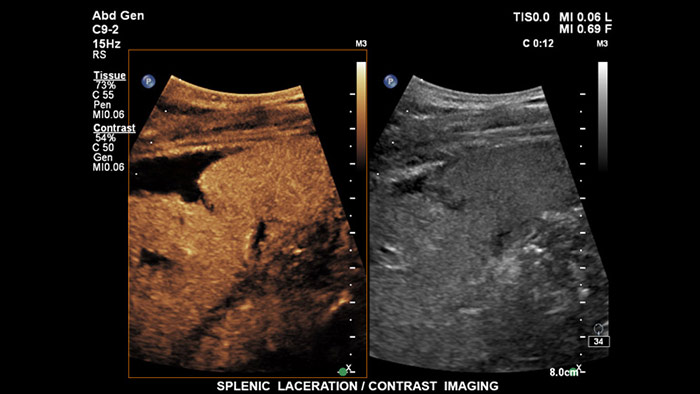

A tecnologia de cristais PureWave representa a maior inovação em material de transdutores piezoelétricos dos últimos 40 anos. Os cristais puros e uniformes do PureWave são 85% mais eficientes do que o material piezoelétrico convencional, o que resulta num desempenho excecional. Esta tecnologia é parte integrante dos nossos transdutores C5-1, C9-2 e X6-1, permitindo uma penetração melhorada em pacientes difíceis enquanto mantém uma excelente resolução de detalhes, sensibilidade Doppler e desempenho de CEUS.

Os agentes de contraste de ultrassom conseguem transformar a função do ultrassom no fígado, permitindo ao utilizador estudar os padrões de melhoria de lesões hepáticas suspeitas em tempo real, proporcionando acesso a diagnósticos com maior rapidez e confiança. Com o EPIQ da Philips, a CEUS está perfeitamente integrada no fluxo de trabalho padrão, fornecendo detalhes excecionais ao longo dos exames de fase arterial, portal e tardia. Além disso, com tecnologias avançadas na ponta dos seus dedos, como o ecrã MaxVue FHD, o transdutor PureWave C9-2, a imagiologia de fusão e a quantificação de Q-App, o EPIQ fornece a máxima confiança na deteção e caraterização de lesões, mesmo nos exames mais difíceis.

Os agentes de contraste de ultrassom conseguem transformar a função do ultrassom, permitindo aos médicos estudar os padrões de melhoria de lesões hepáticas em tempo real, proporcionando diagnósticos mais rápidos e definitivos. Com o ultrassom da Philips, a ultrassom com realce por contraste está perfeitamente integrada no fluxo de trabalho padrão, fornecendo detalhes excecionais.